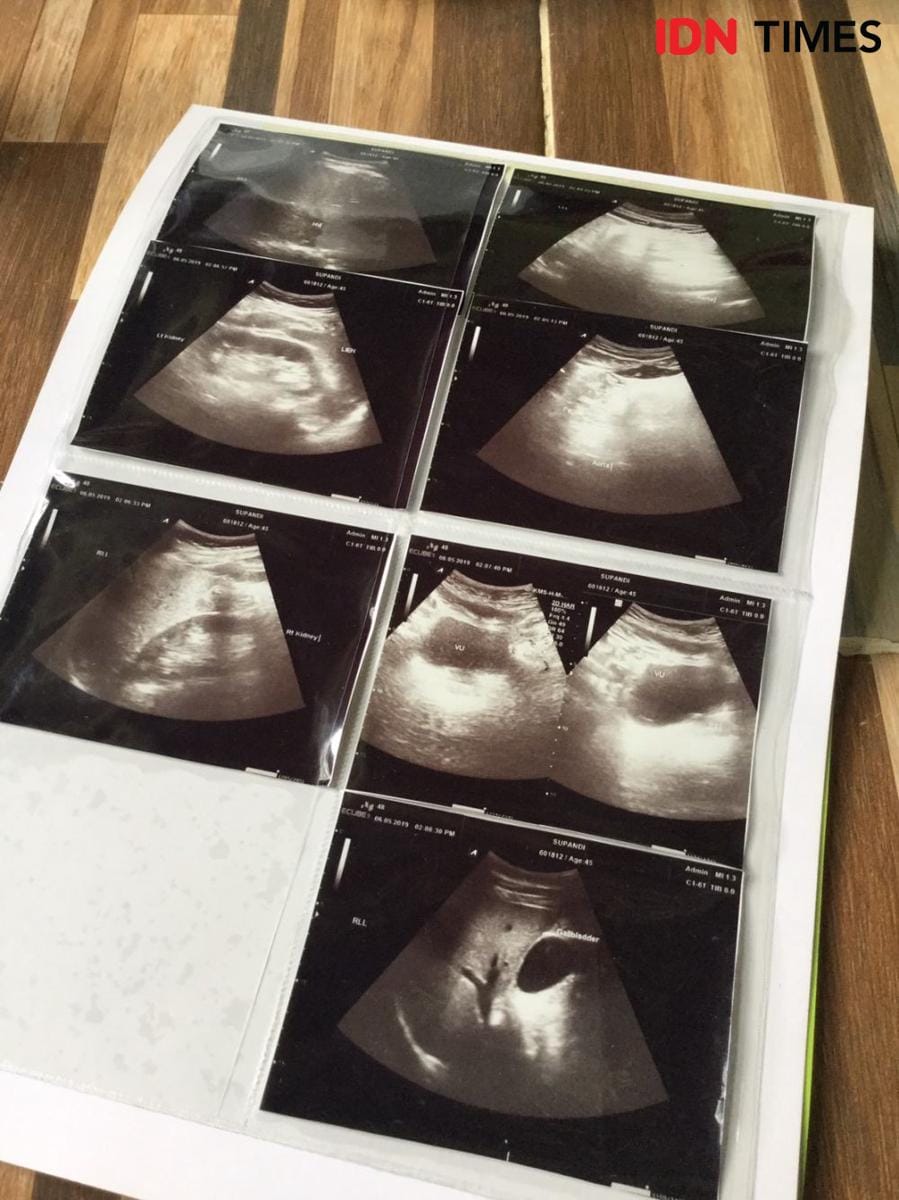

Seminggu setelah kejadian itu, Komar memutuskan ke Puskesmas Bambu Apus. Tapi karena tidak ada alat lengkap untuk mendiagnosa, Komar kemudian dirujuk ke RSUD Tangsel. Dari situ diketahui pria 48 tahun itu mengalami gagal ginjal.

"Karena penanganan RSUD Tangsel kurang baik, lambat, jadi saya cari rumah sakit swasta terdekat. Saya ke Hermina Ciputat di taruh di IGD, benar divonis gagal ginjal bahkan sudah kronis. Saya dirawat di situ, keesokan harinya saya cuci darah," tutur Komar.